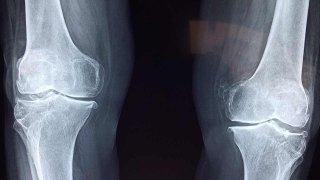

โรคข้อเข่าเสื่อม

ต้องบอกว่าโรคนี้เป็นโรคที่ฮิตมากในผู้สูงอายุบางคนประสบปัญหากับเรื่องเขามากๆไม่ว่าจะเดินยืนหรือนั่งก็ส่งผลกระทบต่อการเจ็บปวดของข้อเข่า ดังนั้นวันนี้เราจะมาให้ความรู้เกี่ยวกับเรื่องข้อเข่าเสื่อมว่าเกิดจากอะไรและเราสามารถดูแลป้องกันได้ด้วยวิธีไหนบ้างอย่ารอช้าต้องตาม ต้องตาม... โครงสร้างของข้อเข่าเขาจะประกอบไปด้วยกระดูก 3 ชิ้นด้วยกันคือ 1 กระดูกต้นขา 2 กระดูกหน้าแข้ง 3 กระดูกสะบ้าระหว่างกระดูกต้นขาและ.. ดูเพิ่ม

ข้อที่เสื่อมจะสามารถรักษาจนหายขาดได้มั้ยคะ

อยากทราบว่าข้อเข่าที่เสื่อม เราสามารถรักษาจนหายขาดได้มั้ยคะ แล้วมีวิธีไหนช่วยได้บ้าง ขอคำแนะนำหน่อยนะคะ ดูเพิ่ม